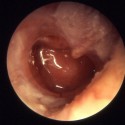

Болезни ушей

ТугоухостьТугоухостью называют нарушения слуха, вызывающие неспособность воспринимать звуки. Может провоцироваться пороками развития, инфекциями, травмами, лекарственными препаратами и другими причинами. Основной метод лечения – слухопротезирование.